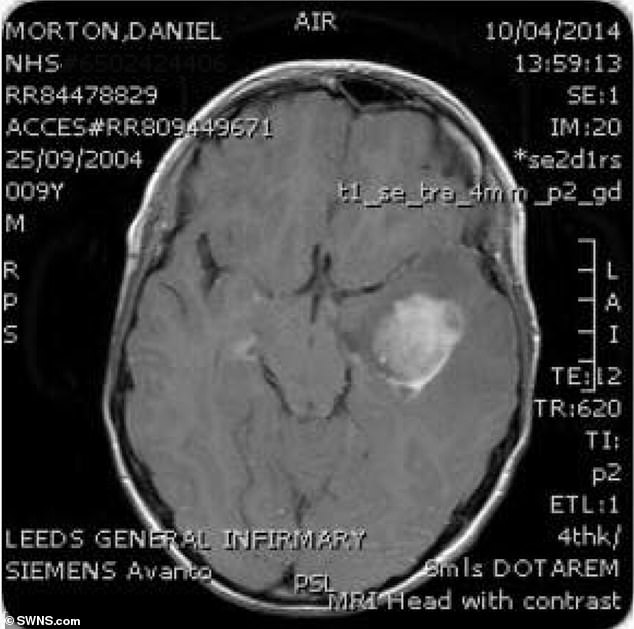

Το 2014 όταν ήταν μόλις 10 ετών διαγνώστηκε με όγκο στο κεφάλι. Ο μικρός Μόρτον έκανε χειρουργείο διάρκειας 11 ωρών για να του τον αφαιρέσουν. Δέκα μέρες αργότερα, του έκαναν επαναληπτικές εξετάσεις, ώστε να δουν την κατάσταση της υγείας του και οι γιατροί διαπίστωσαν ότι το μέγεθος του όγκου μεγάλωνε συνεχώς. Έτσι οι γιατροί εκτιμούσαν ότι αγόρι δεν θα είχε περισσότερο από 18 μήνες ζωής….

Έναν μήνα αργότερα, η οικογένεια του Ντάνιελ επικοινώνησε με μια ερευνητική ομάδα στη Γαλλία, κάνοντας μια τελευταία προσπάθεια για να σώσουν το παιδί. Οι νέες εξετάσεις έδειξαν ότι ο Ντάνιελ δεν είχε φτάσει ακόμη σε τελικό στάδιο. Τα αποτελέσματα των εξετάσεων που έδωσαν μια νέα ελπίδα στον Ντάνιελ και την οικογένειά του, επιβεβαιώθηκαν και από τους γιατρούς του νοσοκομείου Great Ormond Street Hospital….